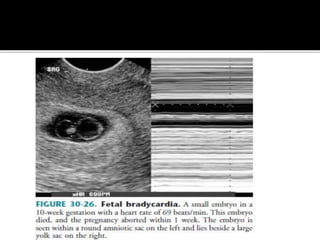

Embryonic bradycardia:

Doubilet and Benson found that a heart rate

less than 80 beats / min in embryos with a

CRL less than 5.0 mm was universally

associated with subsequent embryonic

demise.

Normal : (120 or more beats/ min)